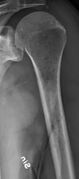

The diagnostic examination of a person with suspected multiple myeloma typically includes a skeletal survey. This is a series of X-rays of the skull, axial skeleton, and proximal long bones. Myeloma activity sometimes appears as "lytic lesions" (with local disappearance of normal bone due to resorption) or as "punched-out lesions" on the skull X-ray ("raindrop skull"). Lesions may also be sclerotic, which is seen as radiodense.[70] Overall, the radiodensity of myeloma is between −30 and 120 Hounsfield units (HU).[71] Magnetic resonance imaging is more sensitive than simple X-rays in the detection of lytic lesions, and may supersede a skeletal survey, especially when vertebral disease is suspected. Occasionally, a CT scan is performed to measure the size of soft-tissue plasmacytomas. Nuclear Medicine Bone scans are typically not of any additional value in the workup of people with myeloma (no new bone formation; lytic lesions not well visualized on nuclear bone scan).

Multiple myeloma in the upper arm

Humerus with multiple myeloma lesions

Same humerus before, with just subtle lesions